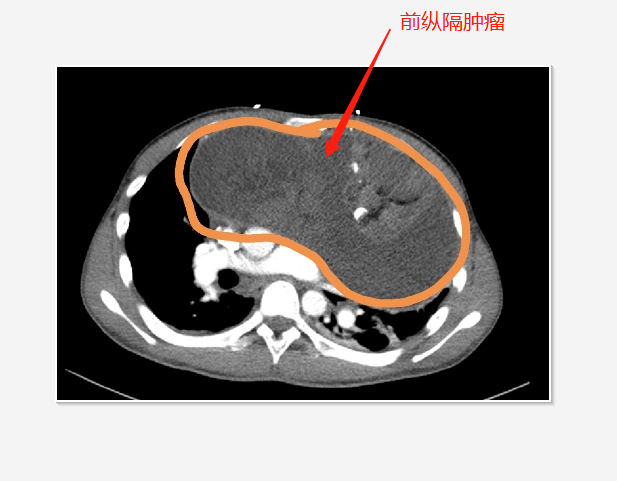

小曹先首先就诊急诊科。经胸外科马少华主任、心脏外科赵鸿医师等联合会诊,小曹被诊断患前纵隔巨大肿瘤,肿瘤直径约20cm,畸胎瘤可能性大,但不排除恶行可能。当天心脏外科医师在急诊室先给小曹进行心包引流,以减轻其心包填塞的症状。

10月12日,小曹被收入胸外科病房。经过充分的术前准备,10月14日,在手术室、麻醉科的支持保障下,胸外科联合心脏外科为小曹手术。胸外科刘丹丹、王京弟医师和心脏外科赵鸿医师,经过近7小时的努力,完整切除了患者胸腔前纵隔肿瘤,进行了心包开窗,并清理了积液及纤维素包裹,同时保护了与肿瘤紧密粘连的主动脉、肺动脉、上腔静脉等大血管,这些大血管未发生损伤出血。